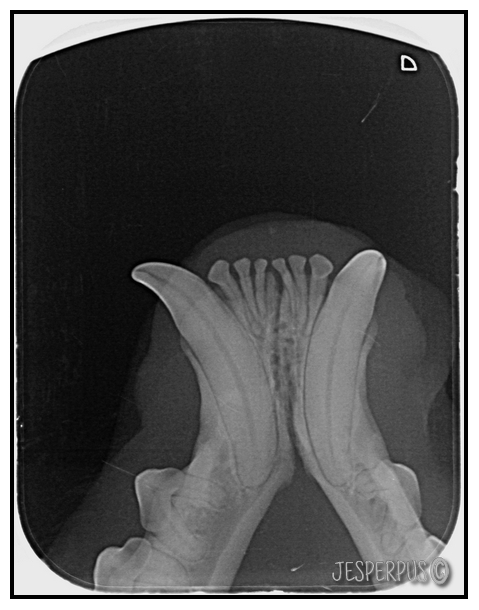

Se og røntgenbilder av katt med alvorlig TR under, tennene er nesten helt smuldret bort!